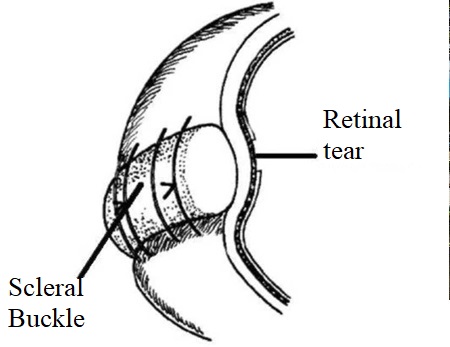

At the initial stage of the disease, there is usually no need to enter the eye, and surgery consists of a local external impression in the projection of the rupture. To do this, use special seals made of soft silicone, which press the area of the gap, thus blocking it.

在疾病的初始阶段,通常不需要进入眼睛,而手术包括在破裂部位投射出局部的外在印象。 为此,请使用由软硅胶制成的特殊密封垫,该密封垫会压住间隙区域,从而阻塞间隙。